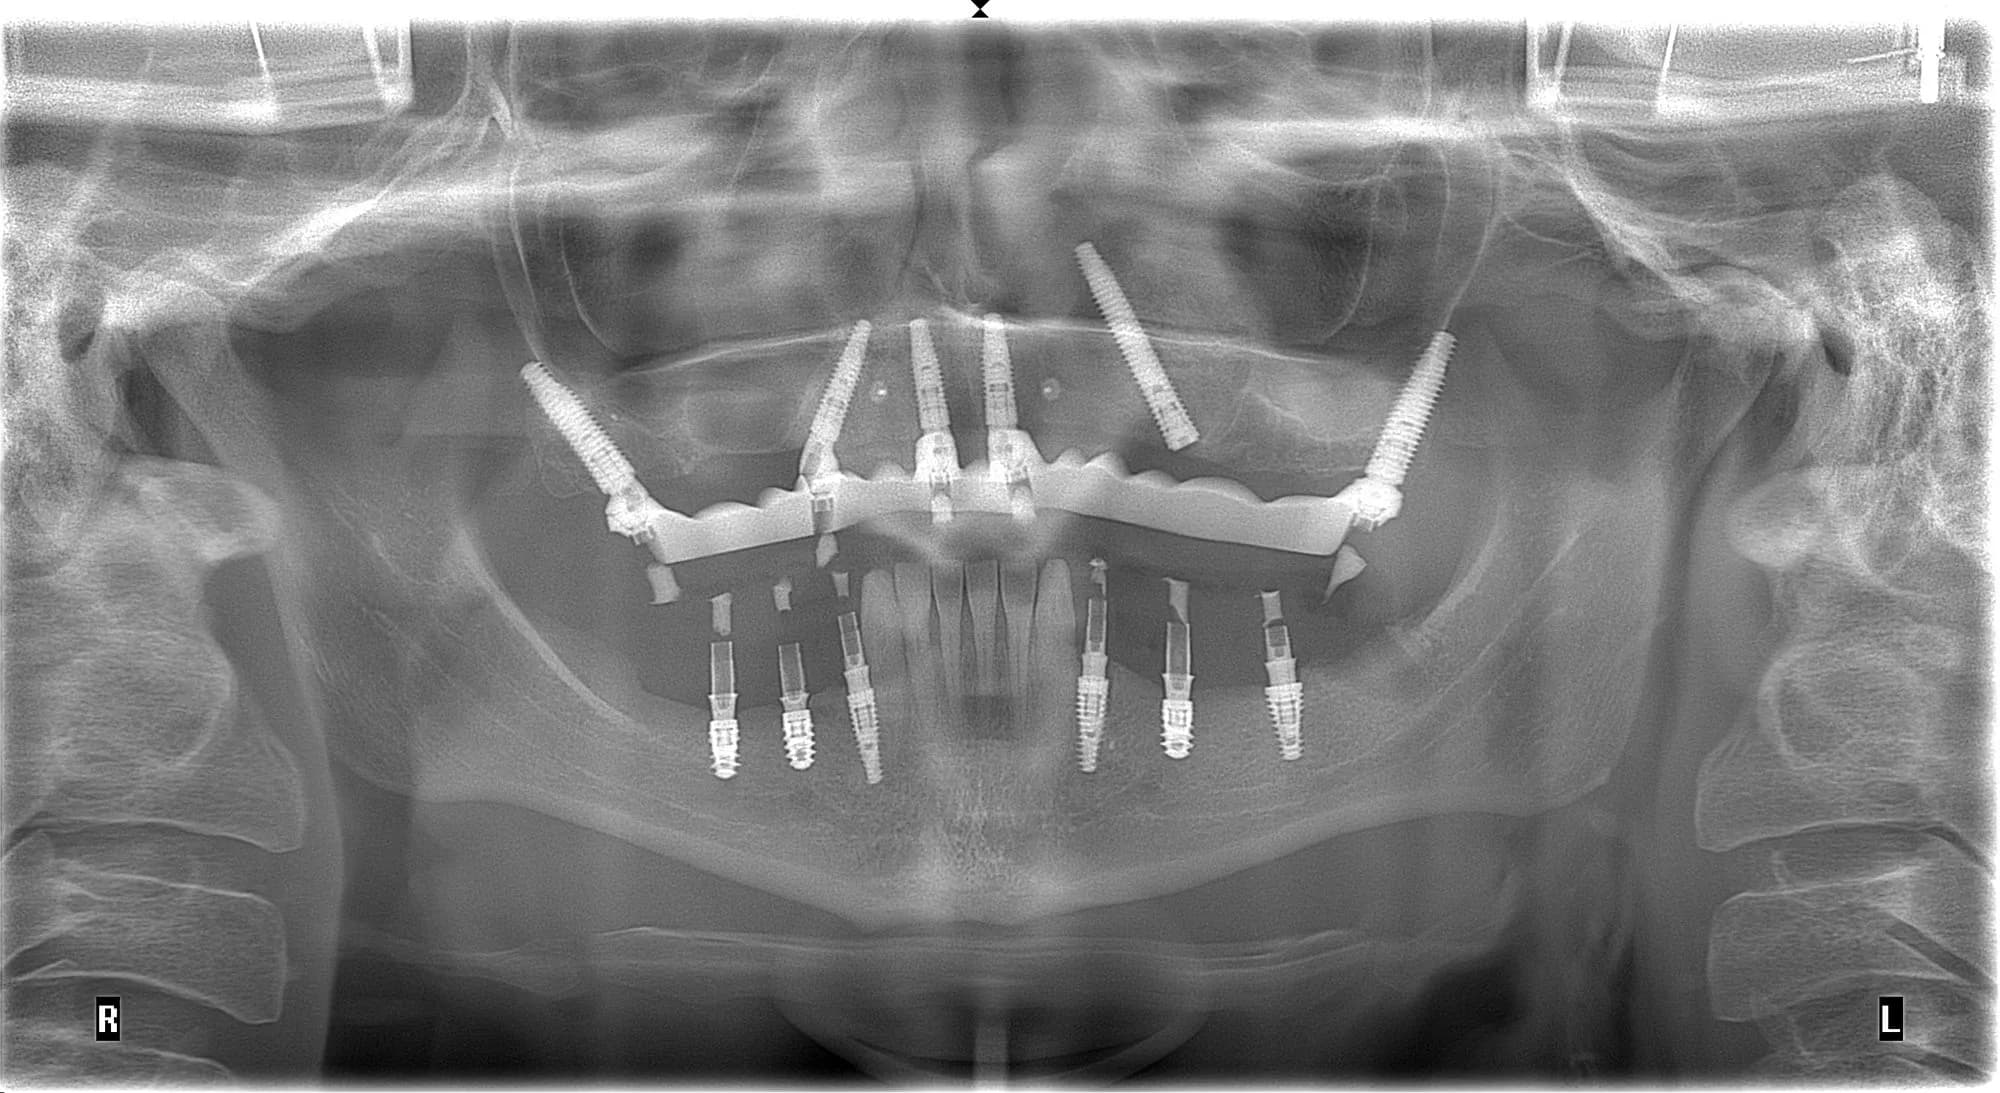

Проблема

Відсутність більшої частини зубів, дефіцит кісткової тканини. Необхідність виконати роботу протягом 7-10 днів.

Рішення

Імплантація за системою All-on-6 на імплантатах NeoDent на верхній щелепі, збереження фронтальних зубів та встановлення імплантатів NeoDent та Straumann на нижню щелепу. Фіксація тимчасового протезу на титановій балці та тимчасовий коронок на імпланті на нижній щелепі

Термін лікування

1 тиждень